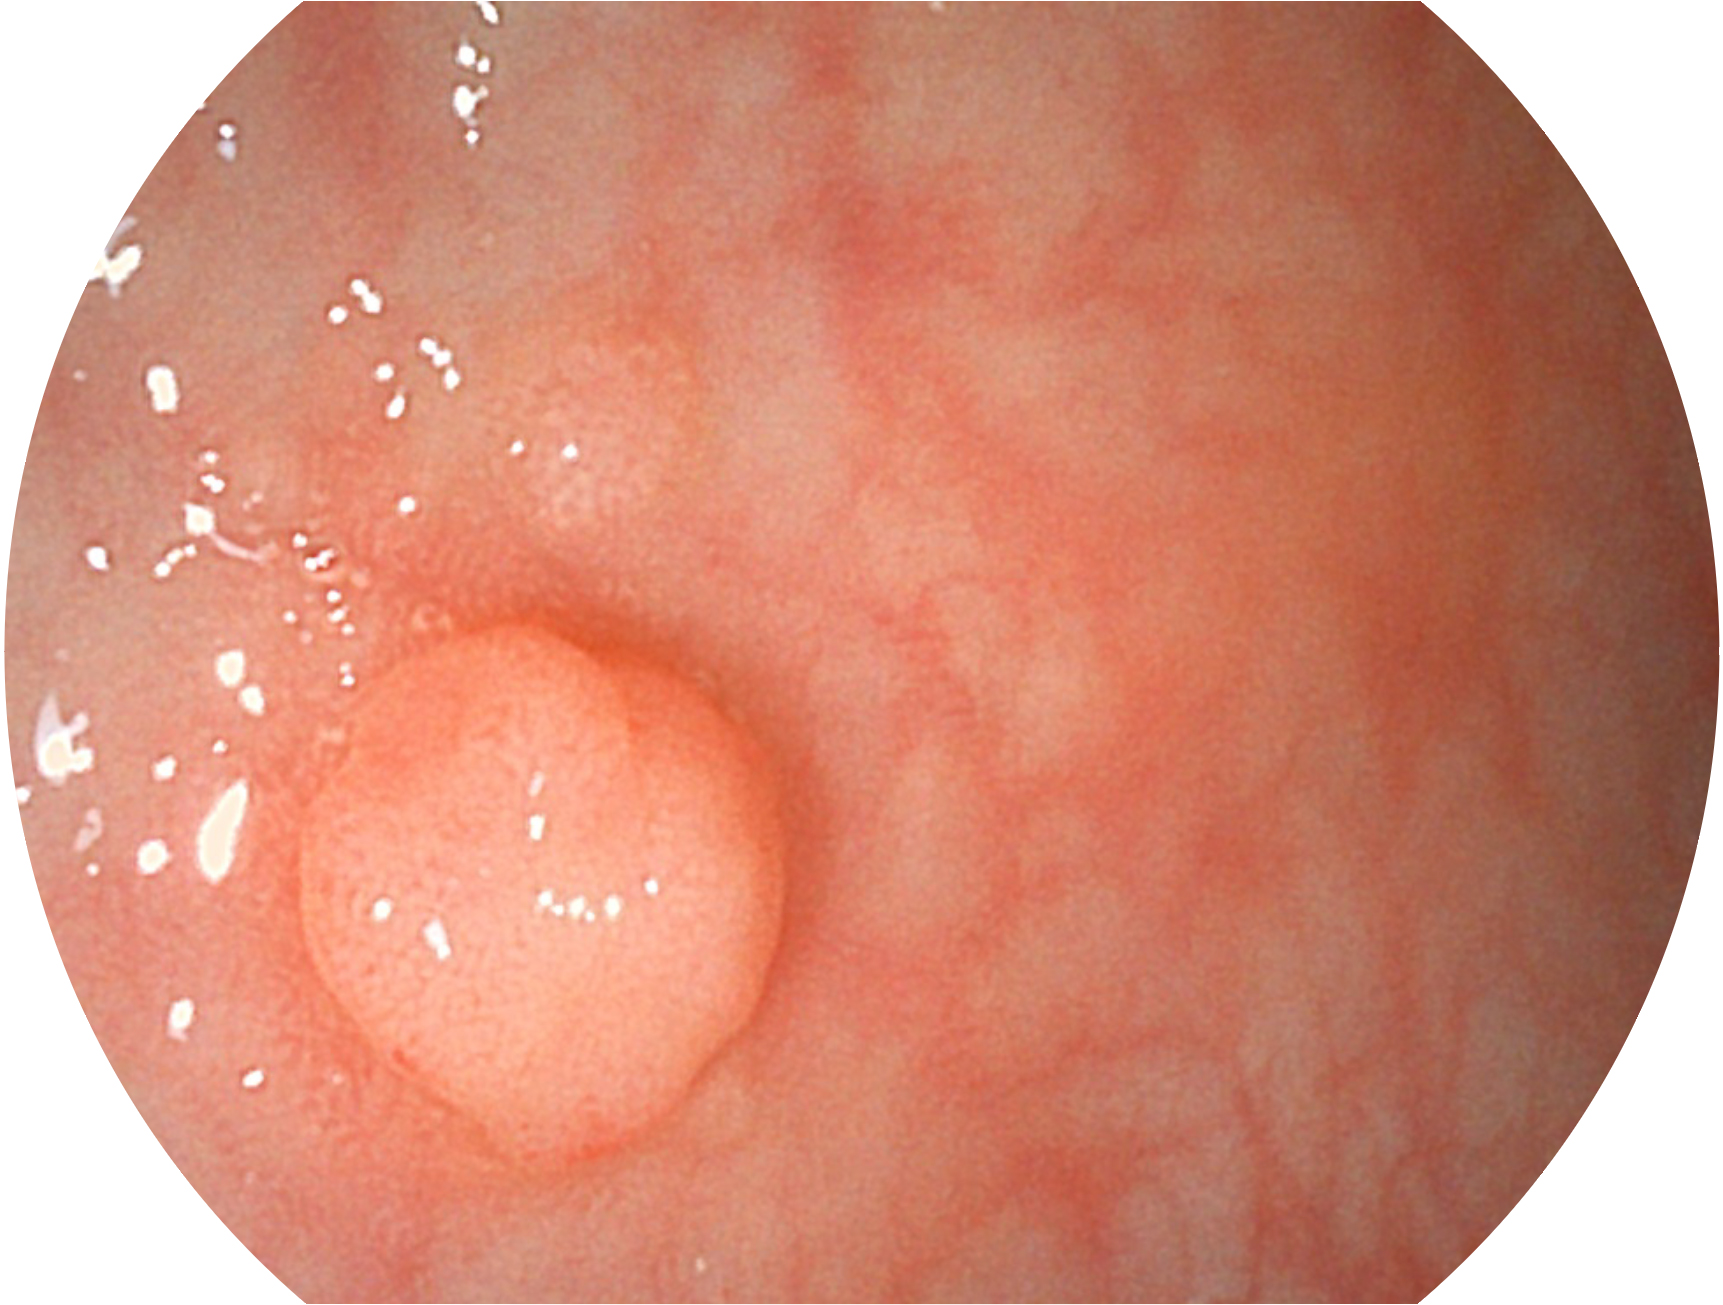

米兰官方网站新开发的内镜染色技术,主要是基于多波长LED 光源的开发,VLS-55Q 四波长LED 光源是由四个不同颜色的LED光按照相应照明模式所规定的特定发光比例进行合束后形成,合束后形成的照明光的光谱由红光、绿光、蓝光及蓝紫光这四个不同的波段范围构成。具有更高光谱自由度,通过光谱比例的控制,实现了聚谱成像技术,英文全称为“Spectral Focused Imaging, SFI”,缩写为“SFI”和光电复合染色成像技术,英文全称为“Versatile Intelligent Staining Technology, VIST”,缩写为“VIST”。